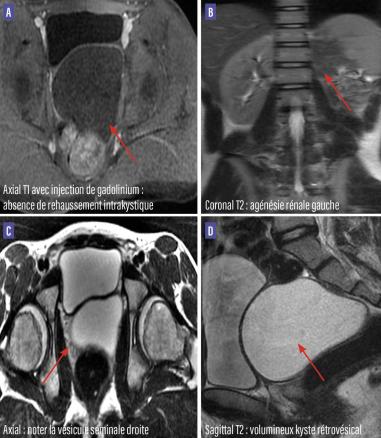

Un jeune homme de 20 ans, sans antécédents particuliers, se plaint de gêne pelvienne minime depuis un an. L’examen clinique et le bilan biologique sont normaux. Une échographie pelvienne initiale révèle une formation kystique rétrovésicale. Une imagerie par résonance magnétique (IRM) secondaire montre une agénésie rénale gauche et l’absence de visualisation de la vésicule séminale gauche, avec la présence d’une volumineuse formation purement kystique rétrovésicale en hypersignal T2, hyposignal T1, à paroi fine sans cloison ou septas (figure). Devant cet aspect, le diagnostic de syndrome de Zinner est retenu.

L’échographie abdominale, la tomodensitométrie et surtout l’IRM sont essentielles pour le diagnostic.2,3